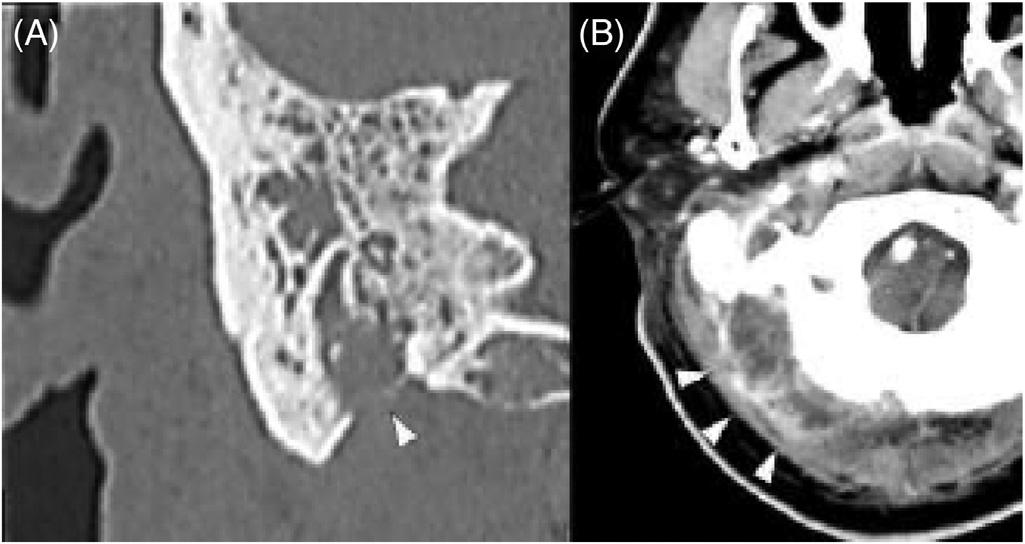

295 Bezold Abscess in a Case of Eosinophilic Otitis Media

Satoshi Tsuruta, Takashi Fujiwara